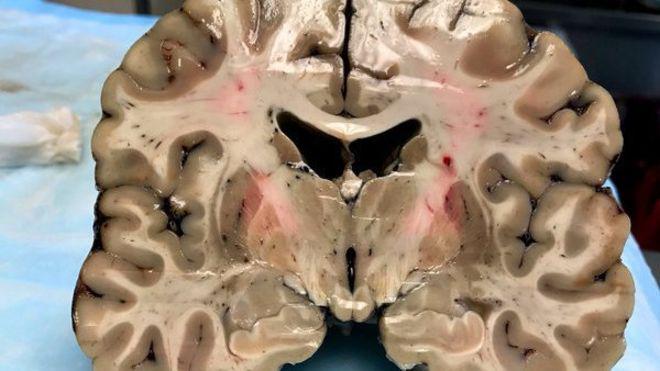

Tras su muerte, Aaron Hernández fue diagnosticado con CTE (chronic trauma encephalopaty), una enfermedad cerebral degenerativa que puede ser causada por un traumatismo craneoencefálico repetido y conduce a síntomas como cambios de humor violentos, depresión y otras dificultades cognitivas.